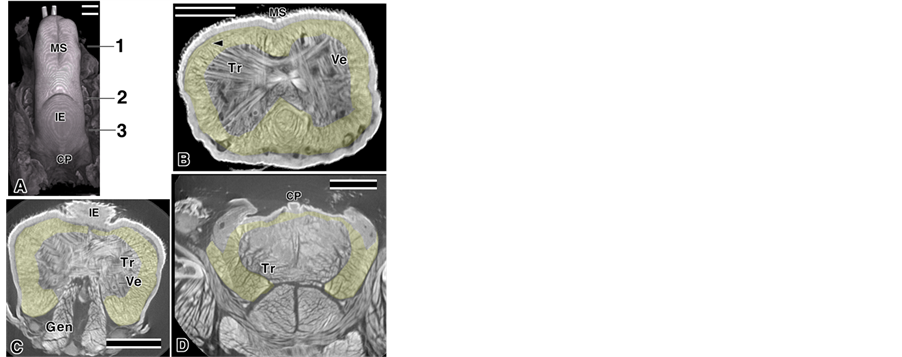

Observations and image processing specimens were scanned using a micro-CT system (SMX-100CTSV, Shimadzu, Kyoto, Japan) as follows: X-ray source 22 kv, 57 mA, pixel size 512, 512, the source to object distance (SOD) 37.6 mm, the source to image-receptor distance (SID) 179.7 mm (Figure 1(A), Figure 5), X-ray source 22 kv, 83 mA, pixel size 512, 512, SOD 13.3 mm, SID 216.3 mm (Figure 1(B), Figure 1(C), Figure 2, Figure 3), X-ray source 22 kv, 56 mA, pixel size 512, 512, SOD 17.5 mm, SID 179.8 mm (Figure 1(D), Figure 4). Micro-CT images were then reconstructed using 3D structural analysis software (MPR, Shimadzu, Kyoto, Japan and TRI/3D BON and FCS4D/VOLvie, Ratoc System Engineering, Tokyo, Japan).

Figure 1. Mouse tongue image using micro-CT yellow; image processing areas. Bar; 10 µm. (A) Dorsal tongue; (B) Coronal cut face at 1; Arrowhead: mST; (C) Coronal cut face at 2; (D) Coronal cut face at 3.

The tongue muscles and their surrounding tissues were recorded using micro-CT and the Aoyagi method [19] . Two types of observation were performed: a low magnification for the entire tongue image (Figure 1(A), Figure 5) and a high magnification for the muscle fascicle images (Figures 1(B)-(D), Figures 2-4). In this study, we focused on the muscle fascicles that ran from anterior to posterior, such as the Lo, Sty, and Hyo. Those muscles were roughly selected in the tomography of the micro-CT and were highlighted in yellow (Figures 1(B)-(D)). Tr present in the region of interest were bypassed in the cases where the Tr ran into the Lo (Figure 1(B) arrowhead). In this research, all epithelium images were cropped by image processing and two types of depictions are presented in the Figs. The first type was a weak transmitted image: the figure near the surface in the 3D images was emphasized and most of the images were this type. The second type was a strong transmitted image: the figures in the deep areas in the 3D image were shown in addition to the surface ones. In several cases, the figures were shown as convergent stereo-pairs of reconstructed images.